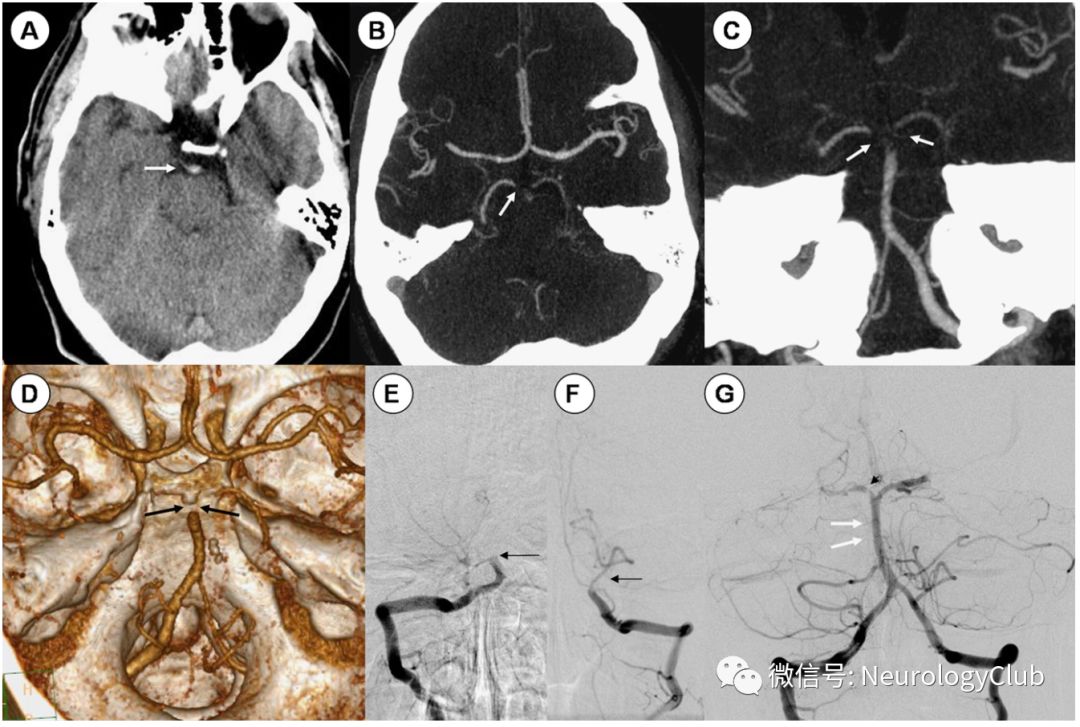

在脑干缺血性卒中的早期CT结果通常是阴性的。基底动脉的高密度影及出血的细微征象都必须仔细寻找。CT血管成像(CTA)是了解发病6小时内的卒中患者颅内血管闭塞情况的有效手段(图6)。其对大血管闭塞的发现和排除较为准确。CT灌注成像(CTP)可通过检测组织水平血流量来发现功能异常,可为溶栓和血管内治疗提供参考。

图6:闭锁综合征;53岁男性患者,表现为突发言语含糊,偏瘫和嗜睡;A:CT平扫可见基底动脉尖高密度;B-D:CTA提示基底动脉血栓形成;E-F:血管造影证实基底动脉闭塞;G:对rt-PA治疗后复查,获得部分再通;注意到右侧大脑后动脉仍有残留血栓

静脉注射重组组织型纤溶酶原激活剂(rt-PA)是卒中发病早期(4.5小时内)有效治疗方法。但实际上目前后循环卒中的时间窗尚未建立。有报道在24小时后仍有部分患者溶栓后症状改善(图6)。但也有一些患者,即使在最初的6小时内积极治疗,也无法从中获益。